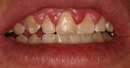

Diş ekimi, kaybedilen dişlerin yerine yapay dişlerin yerleştirilmesi işlemidir. Bu işlem, hem estetik hem de fonksiyonel açıdan birçok avantaj sunmaktadır. Diş ekimi, günümüzde diş hekimliği alanında en yaygın kullanılan yöntemlerden biri haline gelmiştir. Bu makalede, diş ekiminin faydaları detaylı bir şekilde ele alınacaktır. Diş Ekimi Nedir?Diş ekimi, kaybedilen dişlerin yerine cerrahi bir işlemle titanyum veya benzeri malzemelerden yapılan yapay diş köklerinin yerleştirilmesini içeren bir tedavi yöntemidir. Bu işlem, diş kaybının neden olduğu estetik kaygıları gidermenin yanı sıra, çiğneme fonksiyonunu da yeniden kazandırmaktadır. Diş Ekiminin Estetik FaydalarıDiş ekimi, hastaların gülümseme estetiğini önemli ölçüde iyileştirmektedir. Aşağıdaki avantajlar estetik açıdan dikkate değerdir:

Diş Ekiminin Sağlığa FaydalarıDiş ekimi, sadece estetik ve fonksiyonel avantajlar sunmakla kalmaz, aynı zamanda sağlık açısından da faydalar sağlar:

Diş ekimi, günümüzde oldukça yaygın bir işlem olmasına rağmen, her cerrahi müdahalede olduğu gibi bazı riskleri de beraberinde getirebilir. Enfeksiyon ve vücut reddi, bu işlemin potansiyel komplikasyonları arasında yer alır. Ancak, bu riskler uygun önlemlerle önemli ölçüde azaltılabilir.